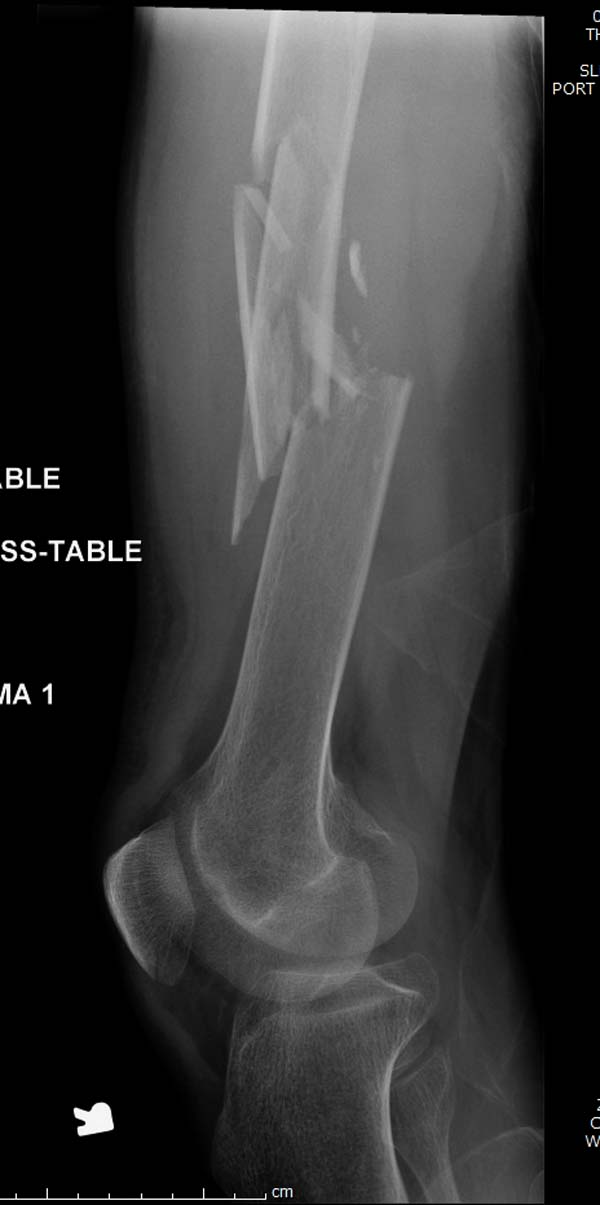

Больному 25 лет, транспортная травма. С детства хроническая почечная

недостаточность, постоянный гемодиализ, находится в листе ожидания на

пересадку почки. Около 4 года назад автоавария с двухсторенним переломом

ацетабулум, которая слева закончилось тотальным протезированием.

Диагноз: переломы бедренных костей, перелом дистального плеча слева,

также неосложненный перелом на уровне грудных позвонков.

Рентген снимки. Хотели услышать примерный алгоритм лечения, c чего

начать и как?

Имя     : 2 Periprosthetic IM nail Lt femur.jpg